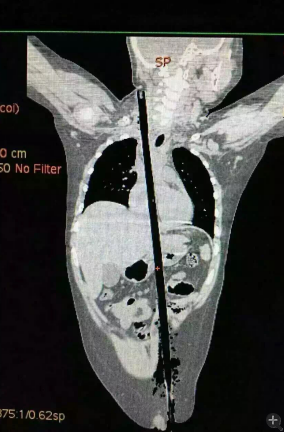

據(jù)相關(guān)知情人介紹,受傷男童24日晚在家中與小朋友一塊兒在墻頭上玩耍時(shí),一不小心從高墻上跌落到了鄰家花圃中,讓人觸目驚心的是,該男童正好跌到了花圃中的一支長約63厘米,直徑約1.5厘米的竹棍上,竹棍自孩子的左側(cè)大腿根部直接插入腹腔并入胸腔直至右側(cè)頸部。

市兒童醫(yī)院組織專家團(tuán)隊(duì)對孩子的病情進(jìn)行檢查、評估后發(fā)現(xiàn),竹棍由患兒左側(cè)大腿根部插入,經(jīng)腹腔穿透胃、肝臟、膈肌入胸腔,并穿透患兒心臟,經(jīng)胸腔入頸部,此刻不能拔除竹棍,因?yàn)槿コ窆鲿䦟?dǎo)致心臟、肝臟破裂大出血導(dǎo)致休克,危及性命。

由于竹棍自心臟的右心房膈面穿入心臟,并由右房近左房頂處穿出心臟,經(jīng)右胸頂刺入右頸部,右心房破口處緊鄰右冠狀動脈,幸運(yùn)的是胸腔內(nèi)大血管無損傷,在體外循環(huán)輔助下,醫(yī)護(hù)團(tuán)隊(duì)異物穿出處鋸斷異物,將插入心臟內(nèi)的竹棍截?cái)喟纬,修補(bǔ)心臟破損處,向上繼續(xù)尋找周圍組織的游離異物,見異物緊臨頸部大血管,經(jīng)精細(xì)手術(shù),終于抽出了異物。整個(gè)手術(shù)時(shí)間花了十多個(gè)小時(shí)。